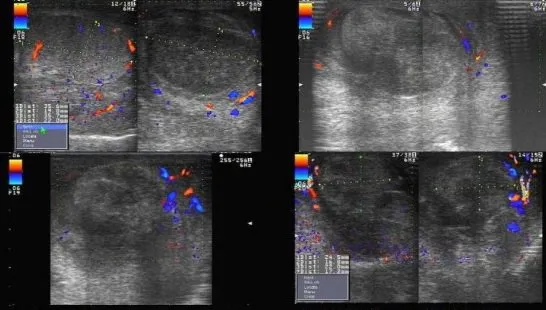

Hình ảnh xoắn tinh hoàn trên siêu âm Doppler màu

4. Hình ảnh xoắn tinh hoàn trên siêu âm Doppler màu

• Giai đoạn cấp tính (1-6 giờ):

• Giảm hoặc không tưới máu tinh hoàn: Trong giai đoạn sớm của xoắn tinh hoàn, siêu âm Doppler màu có thể cho thấy giảm hoặc không có dòng chảy máu trong tinh hoàn bị xoắn.

• Dấu hiệu xoáy nước ở thừng tinh: Dấu hiệu xoáy nước là một dấu hiệu quan trọng cho thấy sự xoắn của thừng tinh.

• Giai đoạn muộn (> 24 giờ):

• Hồi âm không đồng nhất: Khi xoắn tinh hoàn kéo dài, tinh hoàn có thể bị tổn thương và có hồi âm không đồng nhất trên siêu âm.

• Tăng tưới máu mô xung quanh: Trong một số trường hợp, có thể thấy tăng tưới máu ở các mô xung quanh tinh hoàn bị xoắn do phản ứng viêm.